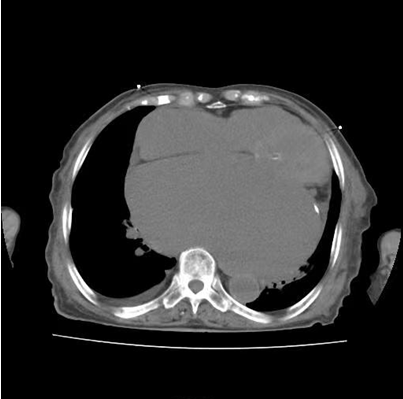

图二:患者胸CT所示巨大左心房

患者因“发作性气短20余年”之主诉入院,多次心脏超声诊断为风湿性心脏瓣膜病二尖瓣狭窄,此次因症状再发加重入院。经评估患者二尖瓣瓣口面积为0.67cm2,二尖瓣跨瓣压差为22mmHg,左房前后径94mm,左右径109mm,为重度风湿性二尖瓣狭窄伴罕见巨大左心房。在心内二科主任寿锡凌带领下,全科室充分讨论。因患者年龄大、基础情况差、无法耐受外科手术治疗,药物治疗不能解除瓣膜狭窄,只能选择经皮二尖瓣球囊扩张成形术。但鉴于患者巨大左心房已使心脏结构发生了巨大变化,单纯通过传统DSA影像结合经胸心脏超声指引下穿刺房间隔引起心脏破裂、心脏填塞、房间隔穿刺部位不佳影响手术操作、二尖瓣狭窄严重难以寻找二尖瓣瓣口、球囊扩张时球囊扩张位置不佳、术中难以即刻评估瓣膜扩张效果等均会导致手术失败进而威胁患者生命。考虑到心腔内超声宛如“心腔内的眼睛”可实时为术者提供心腔内的解剖结构毗邻关系,弥补传统DSA影像结合经胸心脏超声的不足,能为术者决策实时提供指导,确保手术能够安全、准确、顺利完成,最终决定为患者行心腔内超声指引下经皮二尖瓣球囊扩张成形手术。